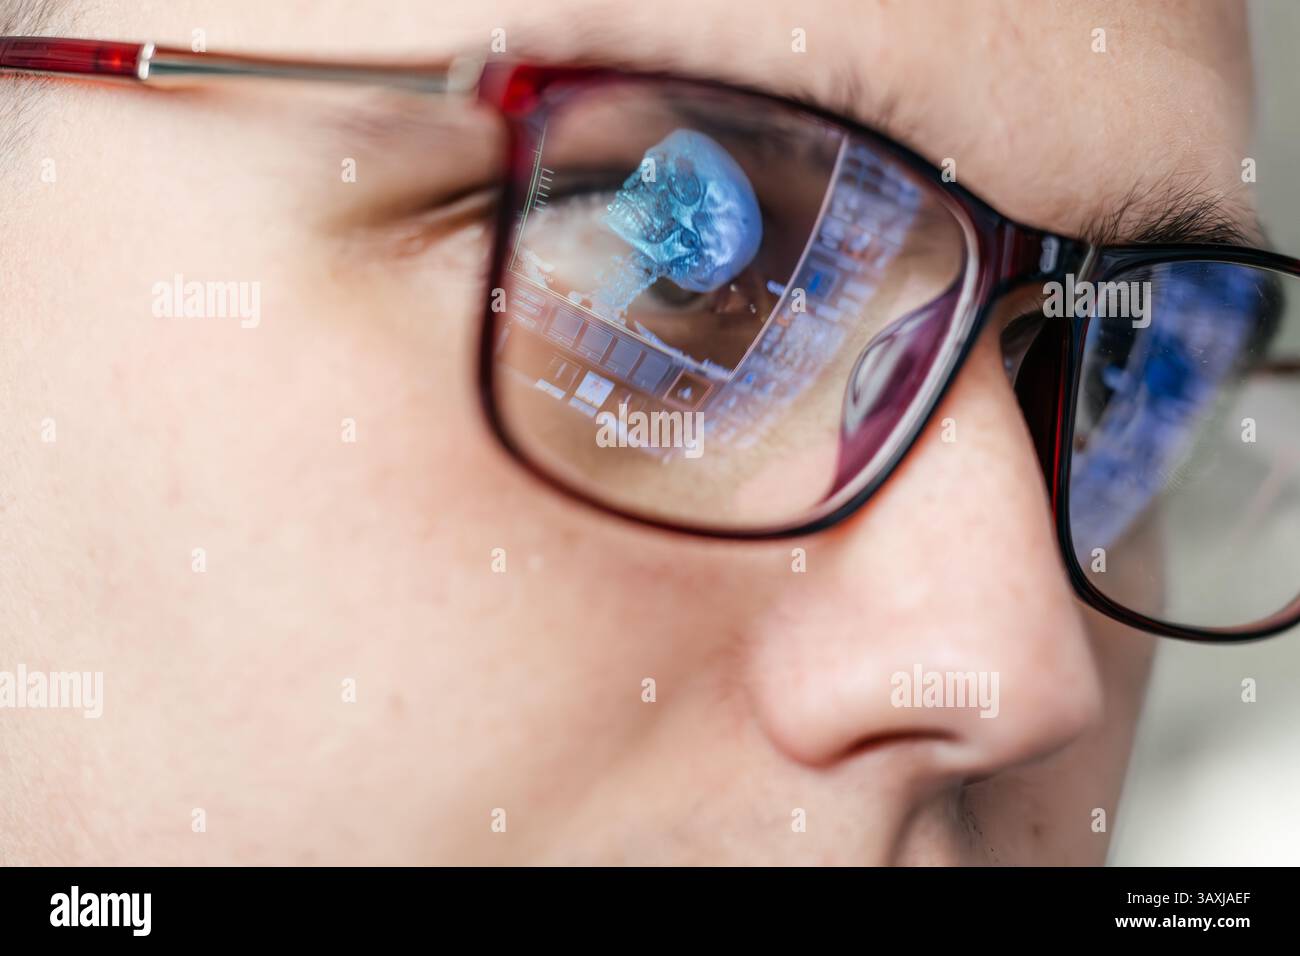

A specialist views MRI scans of the patient's brain, which are reflected in the glasses. The concept of modern technology and accurate diagnosis. Stock Photohttps://www.alamy.com/image-license-details/?v=1https://www.alamy.com/a-specialist-views-mri-scans-of-the-patients-brain-which-are-reflected-in-the-glasses-the-concept-of-modern-technology-and-accurate-diagnosis-image670378423.html

A specialist views MRI scans of the patient's brain, which are reflected in the glasses. The concept of modern technology and accurate diagnosis. Stock Photohttps://www.alamy.com/image-license-details/?v=1https://www.alamy.com/a-specialist-views-mri-scans-of-the-patients-brain-which-are-reflected-in-the-glasses-the-concept-of-modern-technology-and-accurate-diagnosis-image670378423.htmlRF3AXJAEF–A specialist views MRI scans of the patient's brain, which are reflected in the glasses. The concept of modern technology and accurate diagnosis.

A specialist views MRI scans of the patient's brain, which are reflected in the glasses. The concept of modern technology and accurate diagnosis. Stock Photohttps://www.alamy.com/image-license-details/?v=1https://www.alamy.com/a-specialist-views-mri-scans-of-the-patients-brain-which-are-reflected-in-the-glasses-the-concept-of-modern-technology-and-accurate-diagnosis-image670380065.html

A specialist views MRI scans of the patient's brain, which are reflected in the glasses. The concept of modern technology and accurate diagnosis. Stock Photohttps://www.alamy.com/image-license-details/?v=1https://www.alamy.com/a-specialist-views-mri-scans-of-the-patients-brain-which-are-reflected-in-the-glasses-the-concept-of-modern-technology-and-accurate-diagnosis-image670380065.htmlRF3AXJCH5–A specialist views MRI scans of the patient's brain, which are reflected in the glasses. The concept of modern technology and accurate diagnosis.

A specialist views MRI scans of the patient's brain, which are reflected in the glasses. The concept of modern technology and accurate diagnosis. Stock Photohttps://www.alamy.com/image-license-details/?v=1https://www.alamy.com/a-specialist-views-mri-scans-of-the-patients-brain-which-are-reflected-in-the-glasses-the-concept-of-modern-technology-and-accurate-diagnosis-image670381721.html

A specialist views MRI scans of the patient's brain, which are reflected in the glasses. The concept of modern technology and accurate diagnosis. Stock Photohttps://www.alamy.com/image-license-details/?v=1https://www.alamy.com/a-specialist-views-mri-scans-of-the-patients-brain-which-are-reflected-in-the-glasses-the-concept-of-modern-technology-and-accurate-diagnosis-image670381721.htmlRF3AXJEM9–A specialist views MRI scans of the patient's brain, which are reflected in the glasses. The concept of modern technology and accurate diagnosis.